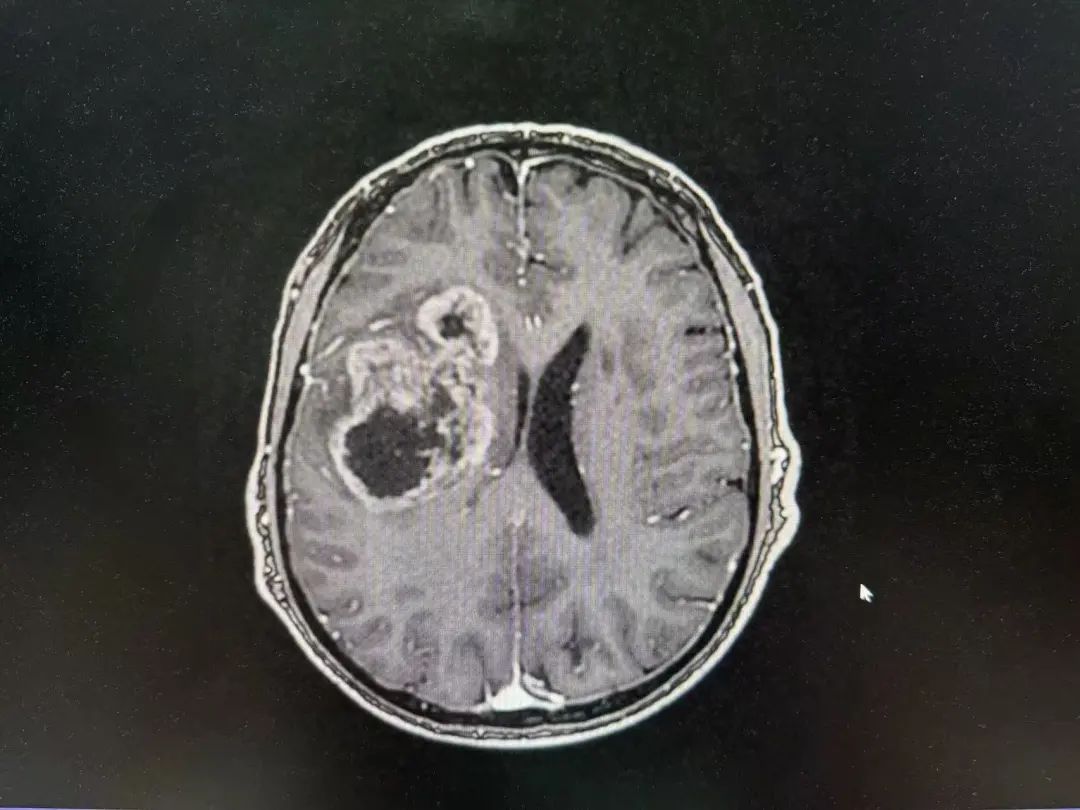

病例特點(diǎn)

男性 | 67歲

主訴:左側(cè)口角流涎10天,左側(cè)肢體無(wú)力7天。

MR:右側(cè)大腦半球腫瘤性病變,考慮高級(jí)別膠質(zhì)瘤(大者大小約3.8cmx4.6cmx3.4cm)。